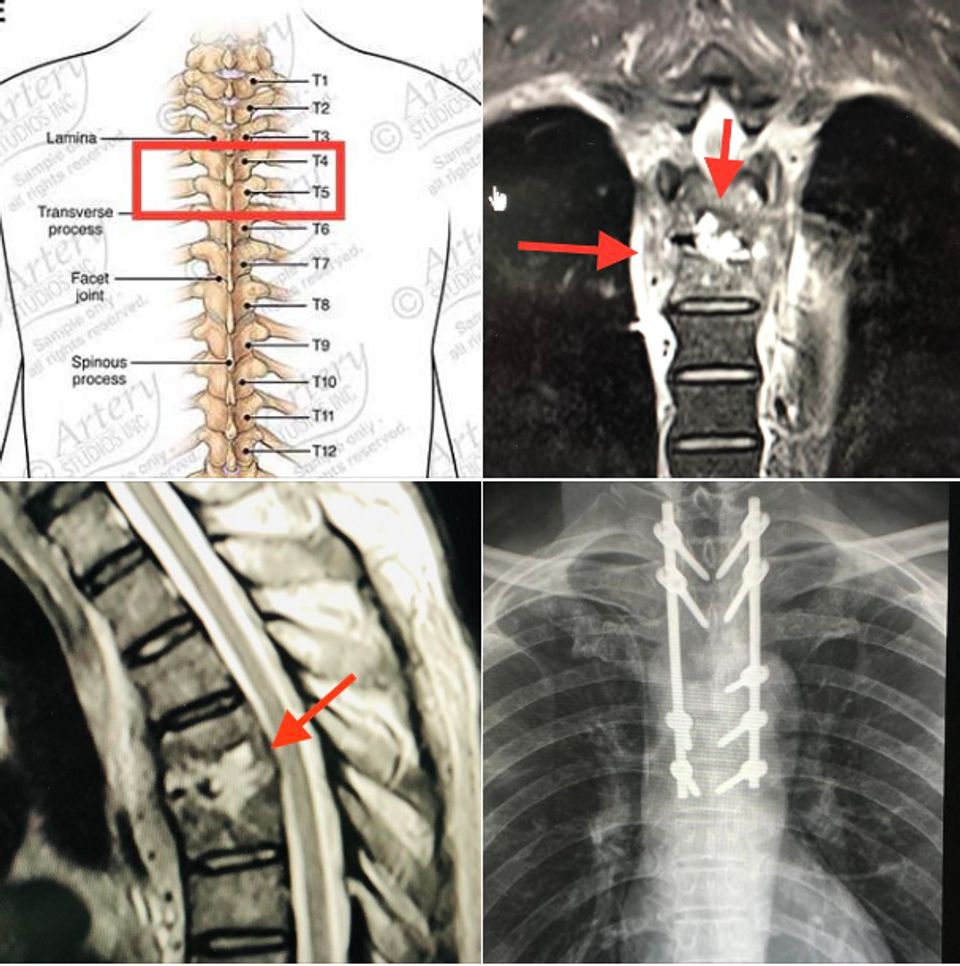

ผู้ป่วยให้ประวัติว่า พี่สาวเคยเป็นวัณโรคปอด 1 ปีก่อน และปฏิเสธการใช้ยาเสพติด ผลตรวจร่างกายปกติ แขนขาไม่อ่อนแรง ตรวจเลือดพบเลือดจางเล็กน้อย เม็ดเลือดขาวปกติ เอกซเรย์ปอดปกติ ทำคลื่นแม่เหล็กไฟฟ้ากระดูกสันหลังส่วนอก (MRI thoracic spine) กระดูกสันหลังส่วนอก (thoracic spine) ชิ้นที่ 4 และ 5 และหมอนรองกระดูกบางส่วนถูกทำลาย และสงสัยมีการอักเสบเนื้อเยื่อรอบๆกระดูกสันหลังส่วนอกชิ้นที่ 4 และ 5 ร่วมด้วย

64eea84b5cf638.82354621.PNG

แพทย์วินิจฉัยว่าเป็นโรค Spondylodiscitis กระดูกสันหลังและหมอนรองกระดูกสันหลังติดเชื้อแบคทีเรีย Staphylococcus aureus ให้ยาฆ่าเชื้อ Cloxacillin ทางเส้นเลือดและทำการผ่าตัดเอาเนื้อตายจากหมอนรองกระดูกสันหลัง ส่วนอกชิ้นที่ 4 และ 5 ใส่สกรูยึดกระดูกสันหลังชิ้นที่ 2,3,5,6,7 ส่งหมอนรองกระดูกสันหลังเพาะเชื้อ พบเชื้อแบคทีเรีย Staphylococcus aureus ตัวเดียวกับในเลือด ให้ยาปฏิชีวนะทางเส้นเลือดนาน 8 สัปดาห์ คนไข้ดีขึ้น ไม่มีไข้ ไม่ปวดหลัง เดินได้ดีขึ้น